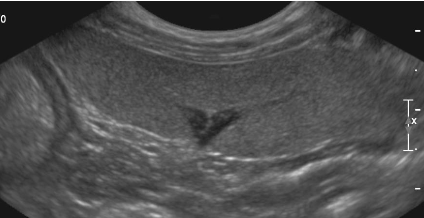

10 - De quel organe s'agit-il ?

A - Le Foie

B - La Rate

C - La Prostate

D - Le Jéjunum

E - Le Pancréas

11 - Sur cette même image échographique que pouvez-vous dire ?

A - J'observe la présence d'une hyperéchogénicité du parenchyme

B - Je n'observe aucune anomalie

C - J'observe la présence d'une hypoéchogénicité du parenchyme

D - J'observe la présence d'un effet de masse

12 - De quel organe s'agit-il ?

A - Du Jéjunum

B - Du Duodenum

C - Du Rectum

D - De la Jonction Iléo-Coeco-Colique

E - Du Colon descendant

13 - Sur cette même image échographique que pouvez-vous dire ?

A - J'observe la présence d'un iléus mécanique

C - J'observe la présence d'un corps étranger

D - J'observe la présence d'un effet de masse en périphérie

E - J'observe la présence d'une adénomégalie

14 - Où pouvez vous trouver cette même image échographique ?

A - Entre le Rein Droit et le colon ascendant

B - Entre le Rein Gauche et le colon descendant

C - Entre le Foie et l'Estomac

D - Entre le Rein Droit et la ligne médiane

E - Entre le Rein Gauche et la ligne médiane

Question 10 : Réponse B

Question 11 : Réponse B

Question 12 : Réponse D

Question 13 : Réponse E

Question 14 : Réponse D